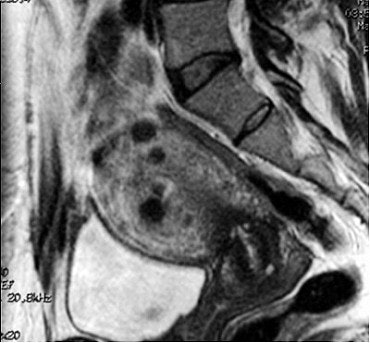

![]() |

| The same patient six months after the UFE procedure. This sagittal, T1-weighted midline MR image shows a 50% decrease in the size of the uterus (white arrow). The fibroids have low signal (black arrow), consistent with devascularization. The patient reported complete relief of symptoms. Image courtesy of Dr. Steven Janney Smith. |